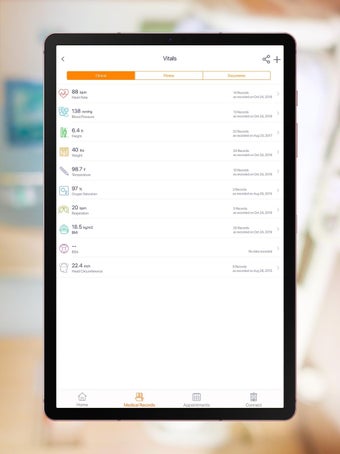

Carepassport là một ứng dụng Android cung cấp cho bệnh nhân một giải pháp toàn diện để quản lý dữ liệu y tế của họ. Ứng dụng cho phép bệnh nhân truy cập và lưu trữ an toàn dữ liệu y tế của mình, lên lịch hẹn, xem hình ảnh y tế, báo cáo xét nghiệm và lâm sàng từ các nhà cung cấp khác nhau, và chia sẻ chúng bằng công nghệ tính toán di động tiên tiến. Với Carepassport, bệnh nhân có thể dễ dàng quản lý nhu cầu chăm sóc sức khỏe của mình chỉ với vài lần chạm trên thiết bị di động của họ.

Một trong những tính năng quan trọng nhất của ứng dụng là việc truy cập dữ liệu y tế một chạm dễ dàng. Bệnh nhân có thể truy cập dữ liệu y tế của mình hoặc dữ liệu đại diện gia đình một cách an toàn và nhanh chóng, làm cho nó trở thành một công cụ tuyệt vời để quản lý lịch sử bệnh án của họ. Ứng dụng cũng cho phép người dùng tìm kiếm các phòng khám và bệnh viện gần đó, lên lịch hẹn, và thậm chí nhận chỉ đường đến cuộc hẹn của họ qua Uber. Ngoài ra, bệnh nhân có thể giao tiếp với nhà cung cấp chăm sóc của họ qua tin nhắn an toàn, chia sẻ hình ảnh y tế và cho phép thành viên gia đình truy cập dữ liệu y tế của họ thông qua cài đặt proxy an toàn. Cuối cùng, ứng dụng cung cấp tài liệu giáo dục liên quan đến chăm sóc sức khỏe và có thể kết nối với các thiết bị đeo được hoặc nhập dữ liệu y tế thủ công.